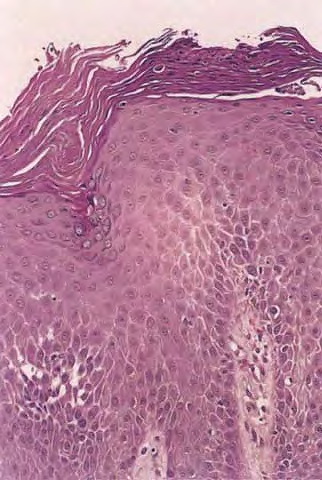

Histopathology. The histopathologic features are a combination of those observed in psoriasis and spongiotic dermatitis. Mild cases may exhibit only slight subacute spongiotic dermatitis. The stratum corneum contains focal parakeratosis, with a predilection for the follicular ostia, a finding known as shoulder parakeratosis . Occasional pyknotic neutrophils are present within parakeratotic foci {neutrophilic parakeratosis}, sometimes with fluid {neutrophilic crust}. There is moderate acanthosis with regular elongation of the rete ridges, mild spongiosis, and focal exocytosis of lymphocytes. The dermis contains a sparse mononuclear cell infiltrate. In HIV-infected patients, the epidermis contains apoptotic keratinocytes, and the dermal infiltrate usually contains plasma cells. |